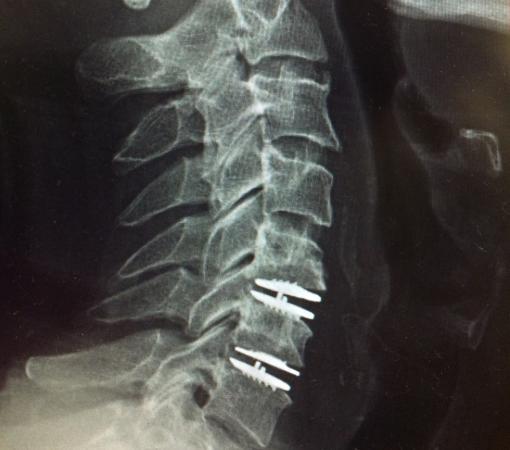

How Is the Surgery Performed?

In disc replacement surgery in Mumbai, the damaged disc is carefully removed and replaced with a high-quality artificial disc. At Synapse Spine, expert surgeons use minimally invasive techniques to ensure faster recovery.